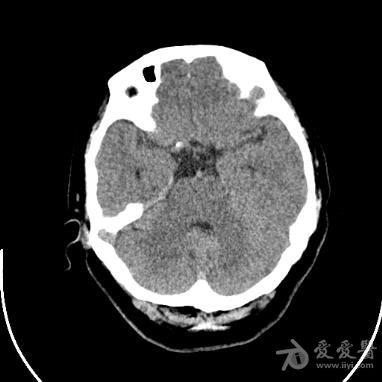

鞍区高密度结节

【讨论】鞍区高密度结节?